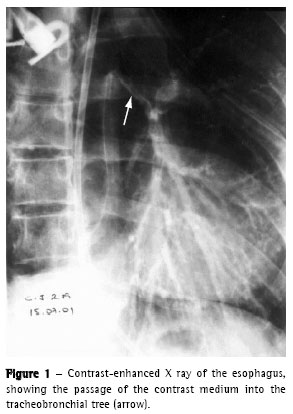

We performed upper digestive endoscopy, which revealed a large fistula between the esophagus and the left bronchus, although the device passed without difficulty (Zagar class 3b(8)). The esophageal mucosa was friable with intense deposits of fibrin. A nasogastric tube was positioned in the second portion of the duodenum (Figure 1).